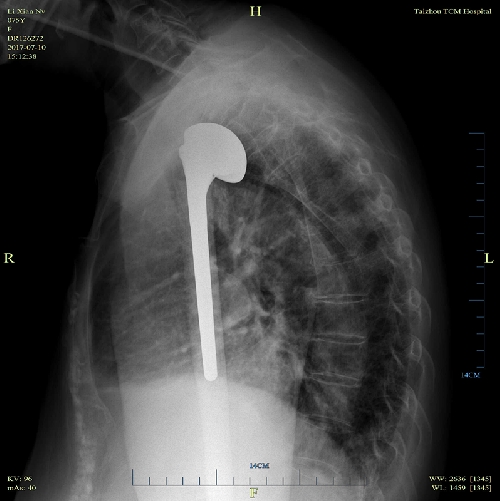

2017年6月29日在全麻下由喻燦明副主任中醫(yī)師主刀,顏峰副主任中醫(yī)師、鄭安華副主任醫(yī)師、丁志清醫(yī)師共同參與下完成了人工肱骨頭置換術(shù),手術(shù)過(guò)程順利。術(shù)后予心電監(jiān)護(hù)、吸氧、血氧飽和度監(jiān)測(cè),常規(guī)預(yù)防感染、護(hù)胃、鎮(zhèn)痛等對(duì)癥治療,患肢頸腕懸吊帶懸吊,在醫(yī)生悉心指導(dǎo)下肩關(guān)節(jié)被動(dòng)外展、上舉鍛煉。

術(shù)后X片正位 術(shù)后穿胸位